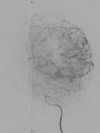

Traumatic intracranial pseudoaneurysms are a rare but severe complication following arterial injury. Pseudoaneurysm formation can occur secondary to blunt or penetrating trauma or iatrogenic injury. We report a case of traumatic pseudoaneurysm secondary to placement of an intracranial pressure (ICP) monitor. A 27-year-old man was involved in a motorcycle accident resulting in multiple intracranial hemorrhages. The patient underwent craniectomy and placement of an ICP monitor. 17 days later he developed dilation of his left pupil, with imaging demonstrating a new hemorrhage in the vicinity of the previous ICP monitor. A cerebral angiogram confirmed a left-sided distal M4 pseudoaneurysm which was treated by n-butyl cyanoacrylate embolization. Intracranial pseudoaneurysm formation following neurosurgical procedures is uncommon. Delayed intracranial hemorrhage in a region of prior intracranial manipulation, even following a procedure as 'routine' as placement of an ICP monitor, should raise the suspicion for this rare but potentially lethal complication.